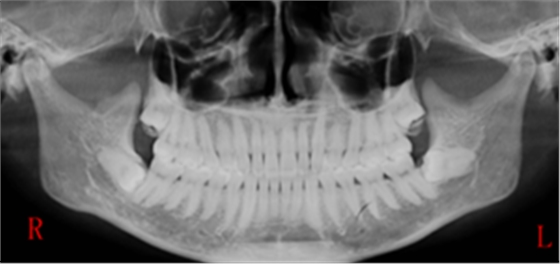

右下智齒去骨范圍如何?分冠線如何?怎樣才能最快時(shí)間能把這顆牙拔出來?

阻生牙的阻力分析及去除阻力的方法問題一:這顆智齒去骨范圍如何?分冠線如何?

答:本x線片示48近中低位埋伏阻生,且牙根緊鄰下牙槽神經(jīng)管,拔除時(shí)需注意充分去除近中方向的牙體冠方阻力及遠(yuǎn)中的牙槽骨阻力,挺出牙根時(shí)盡量做到一次完成,減少牙根與神經(jīng)管的摩擦,降低神經(jīng)受損風(fēng)險(xiǎn)。

遠(yuǎn)中:骨阻力 近中:牙體冠方組織

第一:確定阻力去骨的范圍: